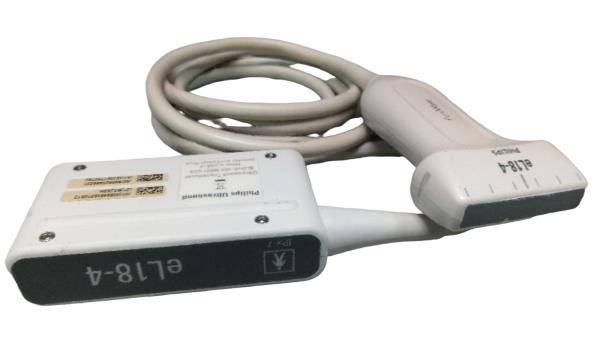

DIAGNOSTIC ULTRASOUND MACHINES FOR SALE

DIAGNOSTIC ULTRASOUND MACHINES FOR SALE

Philips iU22 - A Cart, 3D/4D Ultrasound

Sale price$ 21,585.66